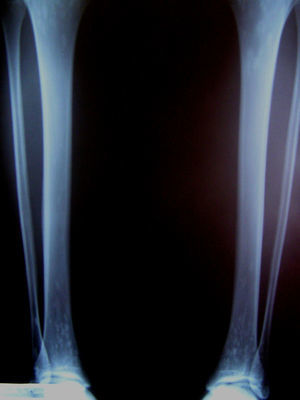

Se realizó una radiografía del tobillo en proyección posteroanterior que descartó fracturas, pero se objetivaron zonas de aumento de densidad radiológica, ovoides y bien definidas, de pequeño diámetro (2–4 mm), en la zona epifisaria distal de tibia y peroné. Para confirmar la sospecha diagnóstica se realiza una radiografía anteroposterior de ambas piernas donde se ven las lesiones simétricas que afectan a las epífisis tanto proximal como distal de ambos huesos (fig. 1).

Clínicamente, es asintomática y no produce deformidad ni alteración en el desarrollo normal óseo por lo que el diagnóstico suele ser un hallazgo radiológico5,6: focos de esclerosis ósea redondeados u ovoideos, rara vez mayores de 10 mm, simétricos, bien definidos, sin afectación de la cortical ósea y con predilección por las epífisis y las metáfisis de los huesos tubulares, carpos, tarsos, pelvis y omóplatos, siendo rara la afectación de las costillas, las clavículas, la columna y el cráneo. Hay, por tanto, una afectación poliostótica (varios huesos) y politópica (distintas partes del hueso)7.